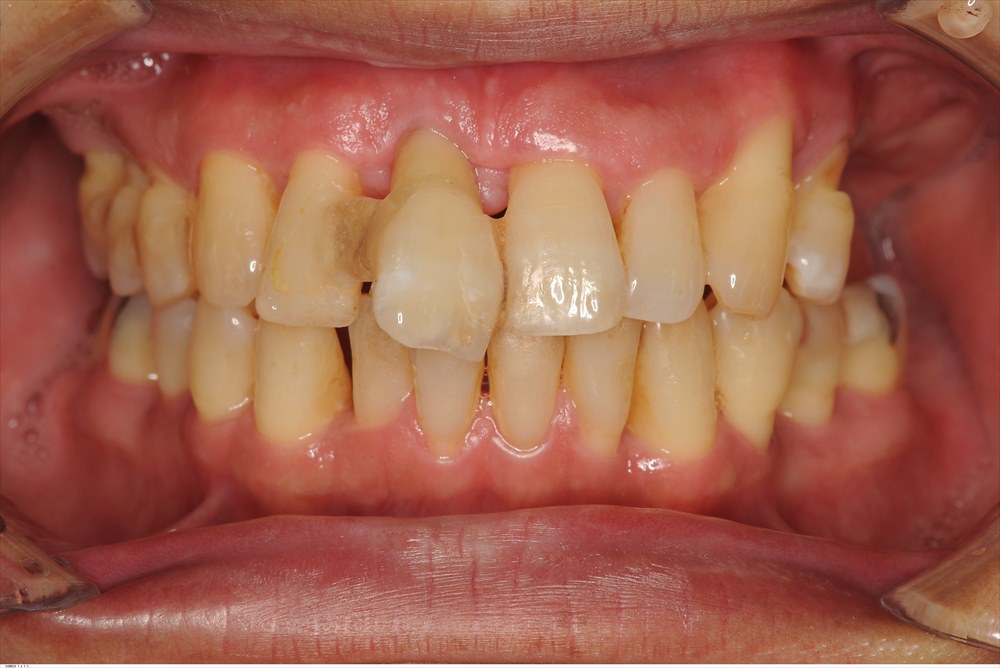

こちらが基本治療を行い、再生治療後6ヶ月のレントゲンです。

再生が認められます。

歯周ポケットも12mmから4mmに改善出血がない状態です。

ここから矯正治療が始まります。